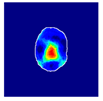

| True label: Crescentic |  |  |  |  |  |

| single-multiclass: Crescentic p = 0.999, IoU = 0.154 | |||||

| multiple-binary: Crescentic p = 1.000, IoU = 0.128 | |||||

| Spatially guided: Crescentic p = 0.979, IoU = 0.740 | |||||